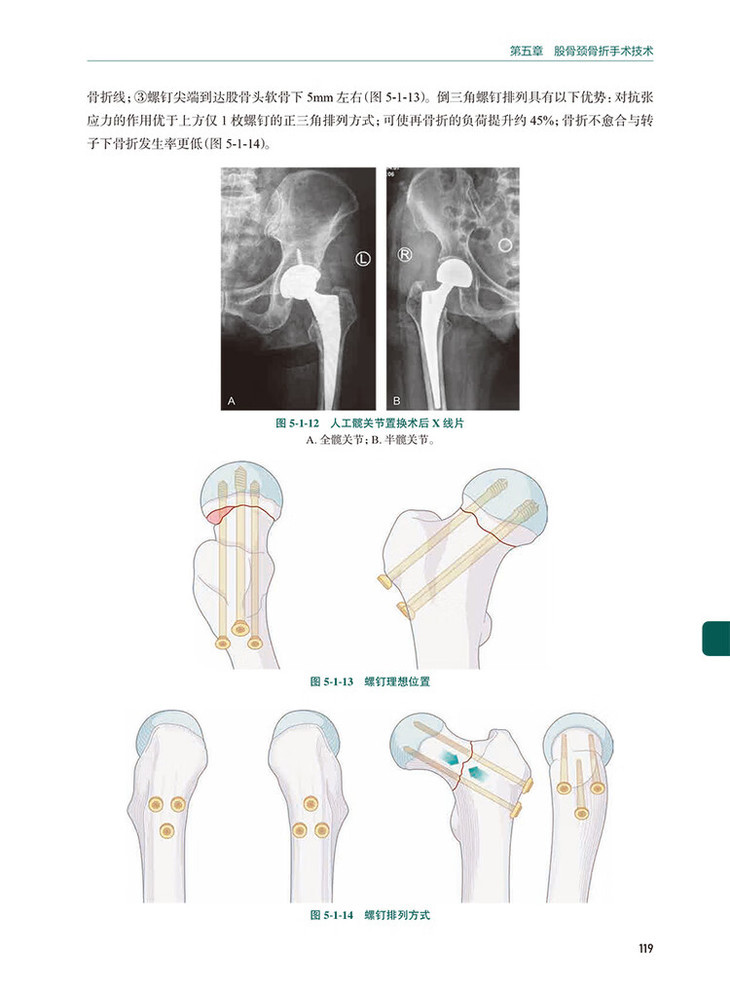

第一节 股骨颈骨折空心螺钉内固定术 /114